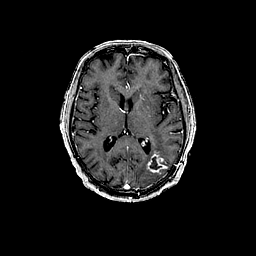

Glioma overlay -- Slice #61

[Home][Help][Clinical] Slice 61